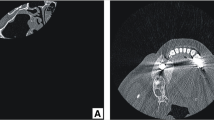

The case-study 2 reports a 68 years old female subject with a maxillofacial deformation resulting from cancer removal. CT scans (Toshiba Aquilion, Toshiba Medical Systems, Japan) are acquired to obtain fundamental information about the deformation and surrounding anatomical structures. The DICOM image-set comprises a total of 215 slices with 1 mm slice thickness and pixel size of 0.351 mm. Similarly to case-study 1, using this CT data, image segmentation process is conducted and a 3-D virtual reconstruction of the patient’s cranium is built. By analysing the model, an absence of part of the zygomatic and superior maxilla bone is observed (Fig. 6a). The 3-D manipulation step is skipped as there are no bone fragments to be repositioned. For sake of comprehension of the patient’s anatomy and malformation, the model is prototyped using SL-stereolithography (Fig. 7a).